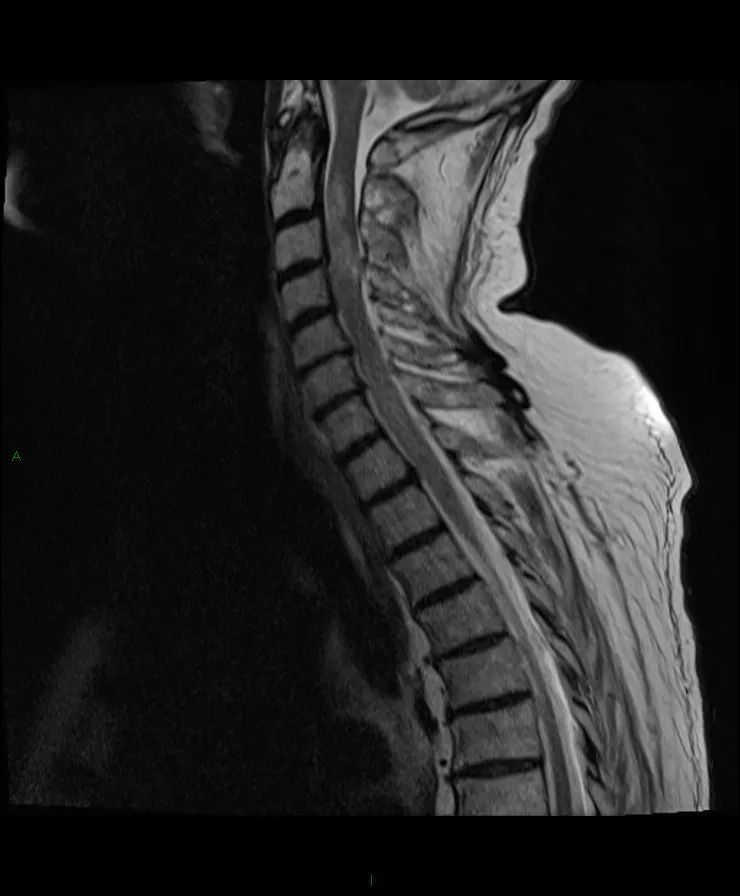

【病例】脊髓星形细胞瘤1例MR影像-2

颈脊髓在C2和T1之间肿块,T1等信号,T2高信号,不规则的非均匀强化。